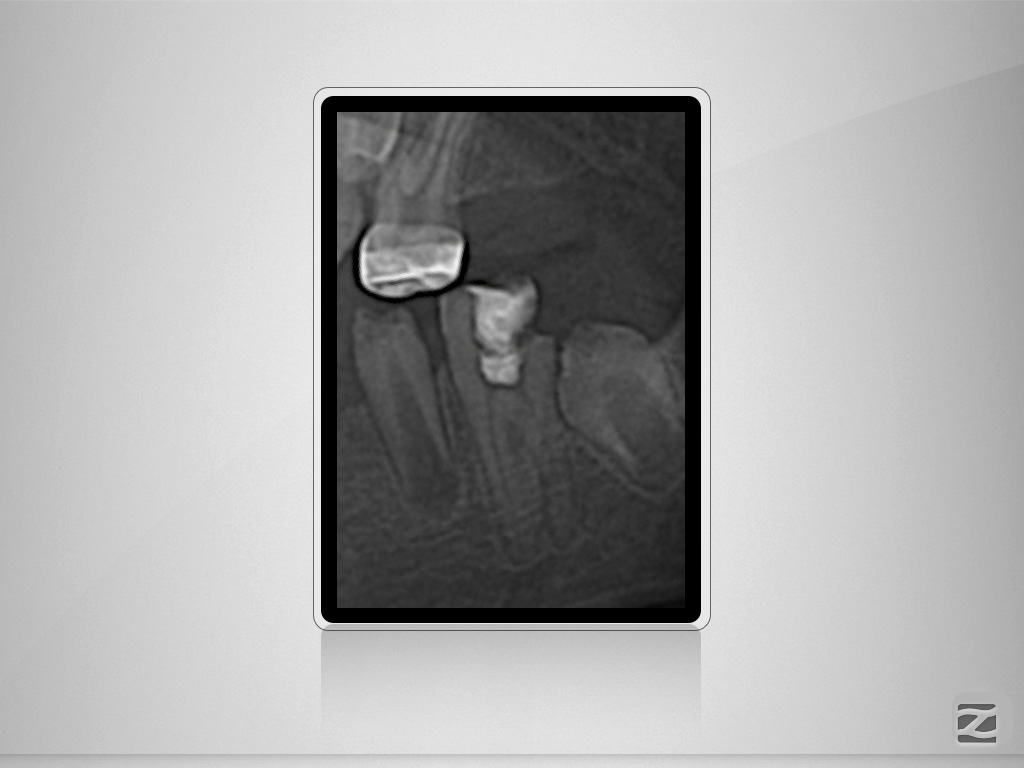

36D.001

Doppeltes C